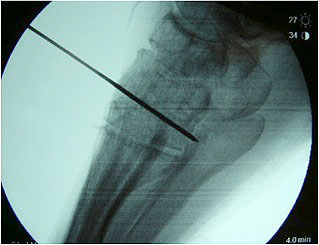

Im Stadium III der Tibialis posterior Sehneninsuffizienz bei fixierter Deformität und/oder erheblich eingeschränkter Inversion im USG aber stabilen und flexiblen Chopart-Gelenk und weniger als 10° fixierter Vorfußsupination eine in-situ oder leicht korrigierende USG-Arthrodese indiziert. Der Vorteil einer isolierten USG-Arthrodese gegenüber einer Triple- oder Double-Arthrodese ist die verbleibende, funktionell wichtige Beweglichkeit in der Chopart-Gelenkreihe. Um einem persistierenden fibulocalcanearem Impingement sicher vorzubeugen, sollte die USG-Arthrodese in maximal 5° Valgus- oder sogar Neutralposition erfolgen. Zur Prophylaxe eines Rezidivs wird die USG-Arthrodese zudem häufig mit einer medialisierende Tuber calcanei Osteotomie und / oder einem FDL-Transfer kombiniert (Abb. 12).